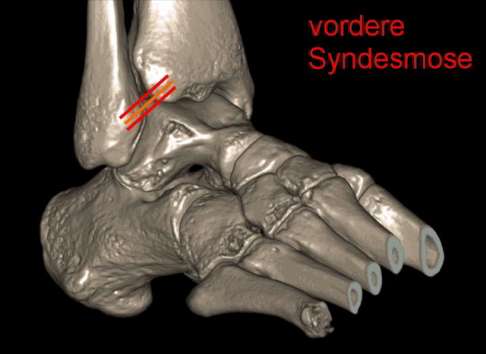

Syndesmosenruptur: Durch Riss des Syndesmosebandes zwischen Schienbein und Wadenbein kann sich die Stellung der Sprunggelenksgabel ändern. © Dr. Thomas Schneider

Diese u-förmige Gabel bildet ein federndes Lager, das durch straffe Bänder gehalten wird. Diese Bindegewebsbrücke (Syndesmose) verleiht dem Gelenk Halt und Stabilität. Anhand der Festigkeit der Syndesmose lässt sich die Schwere von Sprunggelenksverletzungen beurteilen.

DVT-Aufnahme (digitale Volumentomografie) des Sprunggelenks: Gelb eingezeichnet sind die Außenbänder und – zwischen Schienbein und Wadenbein – das Syndesmoseband. © Dr. Thomas Schneider

Das obere Sprunggelenk wird wie alle Gelenke von einer Kapsel umgeben und von Bändern geführt. Man unterscheidet: